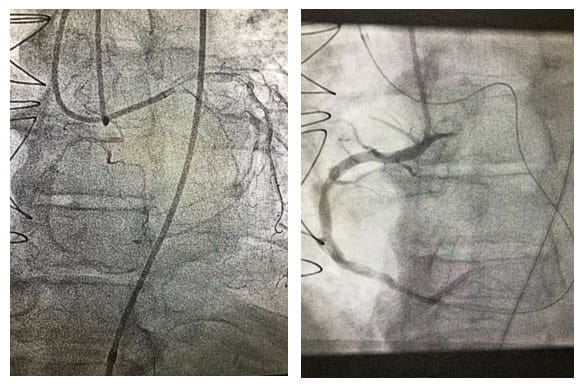

For patients with chronic total occlusion (CTO), a multi-site program stemming from University Hospitals Cleveland Medical Center has demonstrated an annual revascularization success rate of 85 to 90 percent over the past three years.

Performing more than 60 CTO revascularizations per year, University Hospitals Harrington Heart & Vascular Institute is achieving a success rate well above the national average of 55 to 60 percent. Each case requires individual evaluation and precision technique. Often, the heart develops collateral arteries to compensate for the blockage, essentially creating its own bypass. "Sometimes, we actually have to go backwards through these collateral arteries to make a connection and place a stent to open the blockage," Dr. Poommipanit says.